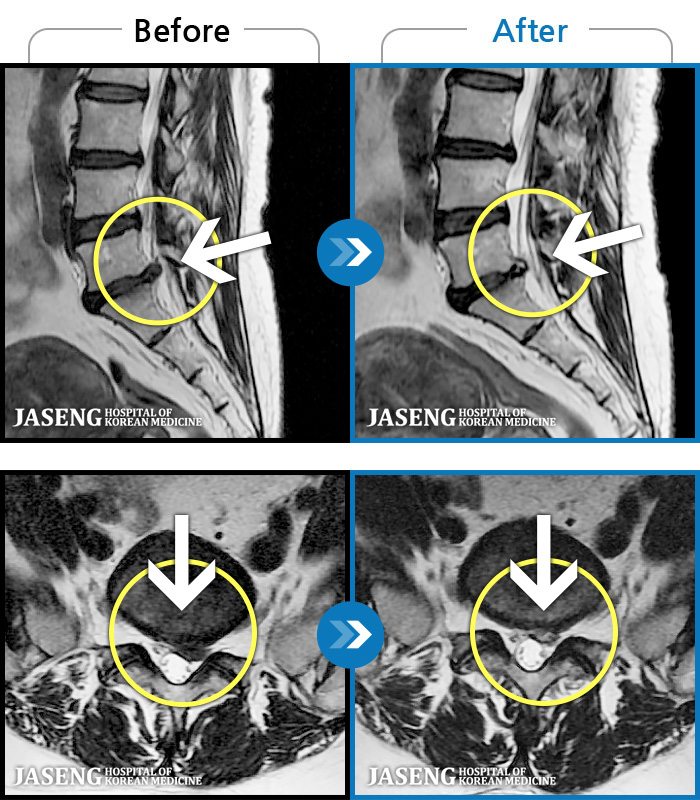

[] 03.04.01~09.11.01

ȯںп Ǹ ǿ ԿǾ, ο ġ ۿ Ƿ ġḦ Ͻñ ٶϴ.